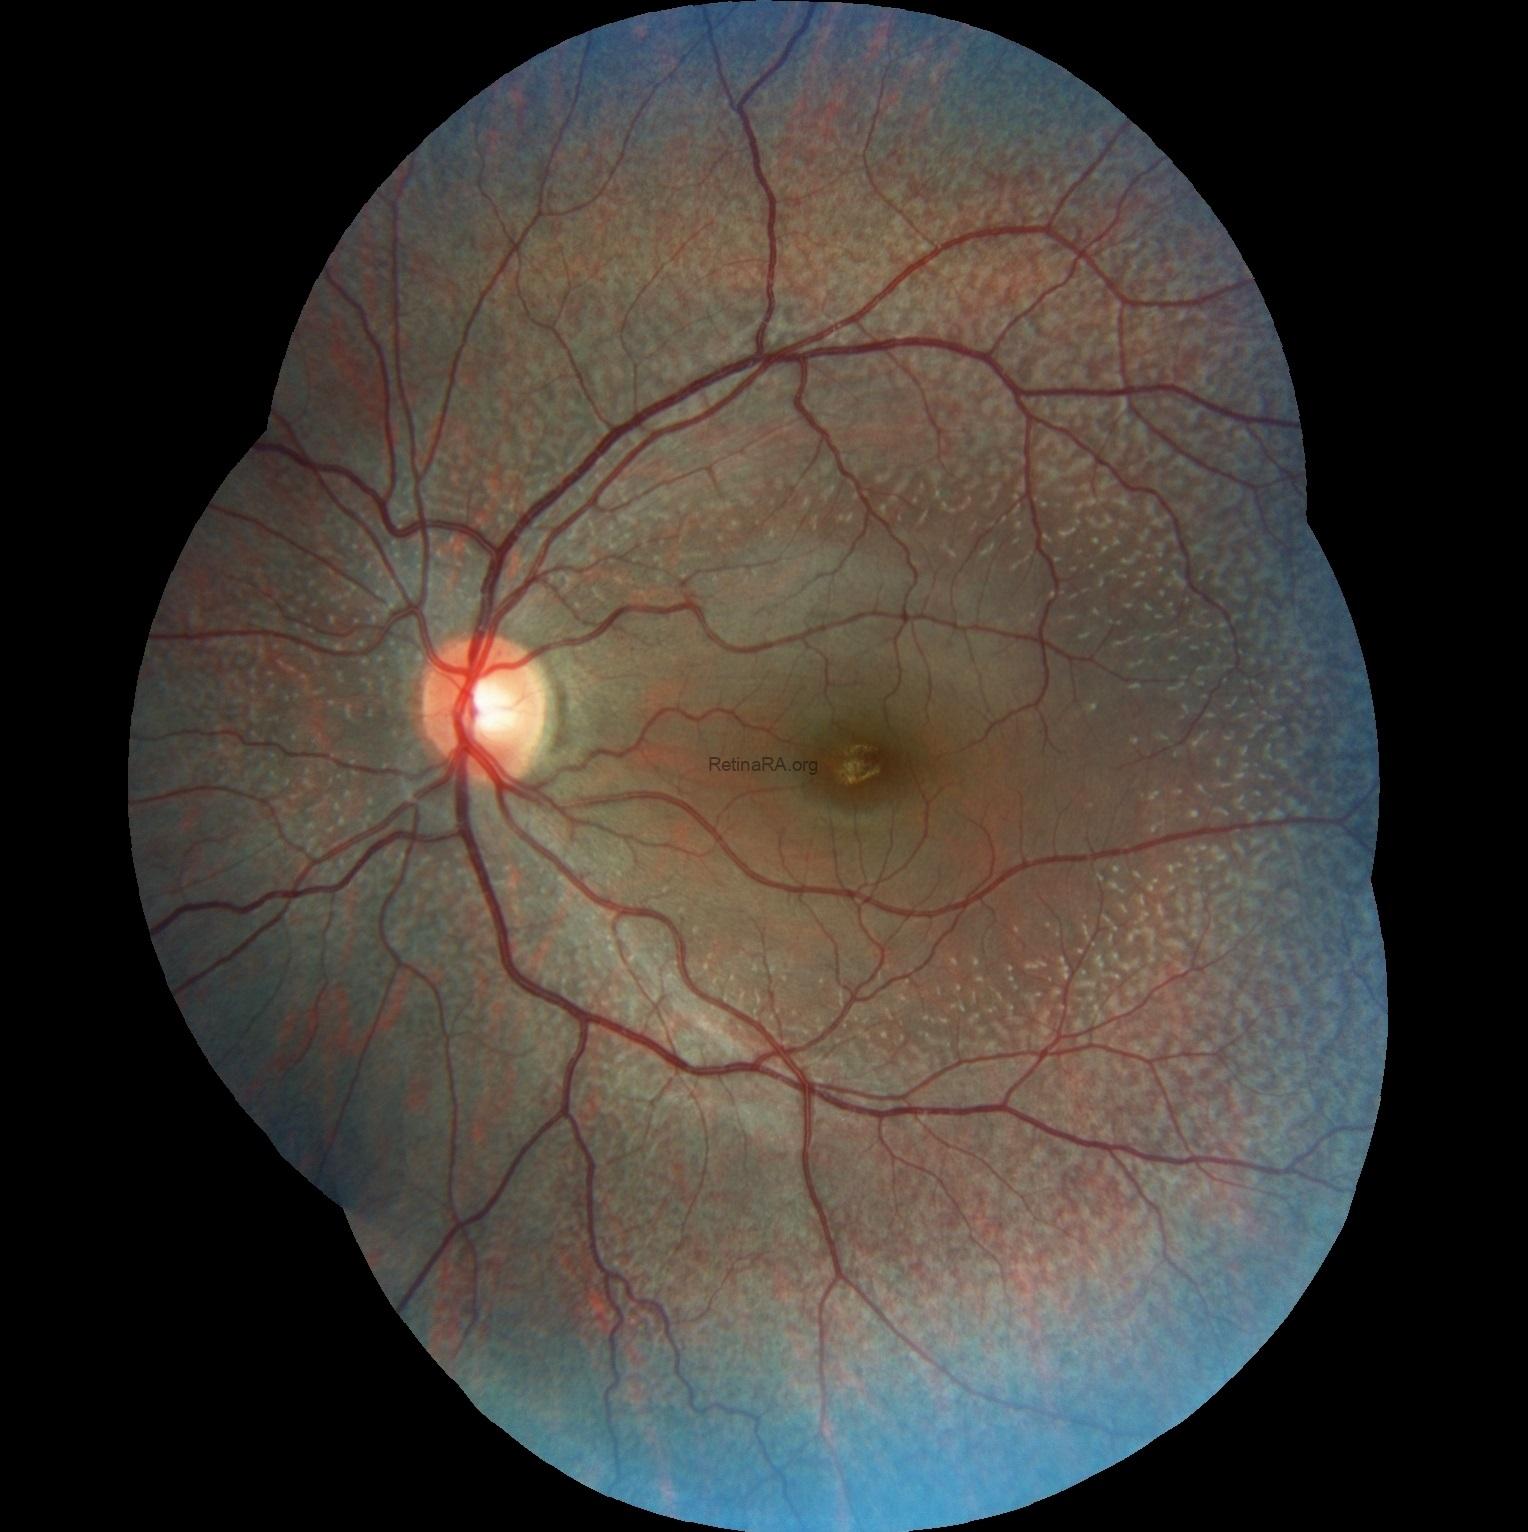

An 18-year-old female complaining of night visual difficulties was referred to our clinic. Her visual acuity was 20/20 in both eyes. She was diagnosed with fundus albipunctatus based on her fundus appearance and autofluorescence image, as well as optical coherence tomography findings. The diagnosis was then confirmed through genetic testing.

Fundus albipunctatus is an uncommon inherited retinal disorder classified within the spectrum of congenital stationary night blindness. It follows an autosomal recessive inheritance pattern and is clinically defined by numerous small white to yellow-white punctate lesions distributed throughout the posterior pole and extending into the mid-peripheral retina, typically sparing the fovea, although macular involvement has been reported in some cases. The condition is most frequently associated with pathogenic variants in the RDH5 gene, which encodes 11-cis retinol dehydrogenase, a key enzyme in the visual (retinoid) cycle responsible for the regeneration of visual pigment.

Ophthalmoscopic examination reveals scattered, discrete yellowish-white dots at the level of the retinal pigment epithelium, predominantly outside the macula. While these lesions are generally stable over time, partial regression has been documented in long-term follow-up. Histopathologically and functionally, these deposits are thought to represent accumulated retinoid intermediates, extending from the RPE–Bruch membrane complex into the outer retinal layers, including the outer nuclear layer.